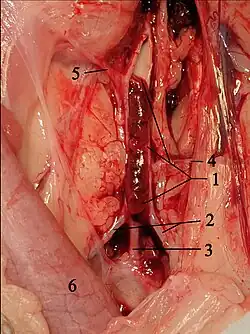

Cardiac catheterization

AO = Descending aorta; LV = Left ventricle; ECG = Electrocardiogram.

After the third QRS complex, the ventricle has more time to fill. Since there is more time to fill, the left ventricle will have more volume at the end of diastole (increased preload). Due to the Frank–Starling law of the heart, the contraction of the left ventricle (and pressure generated by the left ventricle) will be greater on the subsequent beat (beat #4 in this picture). Because of the dynamic nature of the outflow obstruction in HCM, the obstruction increases more than the left ventricular pressure increase. This causes a fall in the aortic pressure as the left ventricular pressure rises (seen as the yellow shaded area in the picture).

Upon cardiac catheterization, catheters can be placed in the left ventricle and the ascending aorta, to measure the pressure difference between these structures. In normal individuals, during ventricular systole, the pressure in the ascending aorta and the left ventricle will equalize, and the aortic valve is open. In individuals with aortic stenosis or with HCM with an outflow tract gradient, there will be a pressure gradient (difference) between the left ventricle and the aorta, with the left ventricular pressure higher than the aortic pressure. This gradient represents the degree of obstruction that has to be overcome to eject blood from the left ventricle.

The Brockenbrough–Braunwald–Morrow sign is observed in individuals with HCM with an outflow tract gradient. This sign can be used to differentiate HCM from aortic stenosis. In individuals with aortic stenosis, after a premature ventricular contraction (PVC), the following ventricular contraction will be more forceful, and the pressure generated in the left ventricle will be higher. Because of the fixed obstruction that the stenotic aortic valve represents, the post-PVC ascending aortic pressure will increase as well. In individuals with HCM, however, the degree of obstruction will increase more than the force of contraction will increase in the post-PVC beat. The result of this is that the left ventricular pressure increases and the ascending aortic pressure decreases, with an increase in the LVOT gradient.

While the Brockenbrough–Braunwald–Morrow sign is most dramatically demonstrated using simultaneous intra-cardiac and intra-aortic catheters, it can be seen on routine physical examination as a decrease in the pulse pressure in the post-PVC beat in individuals with HCM.